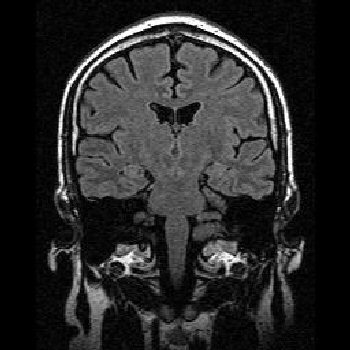

Diag?

Frontotemporal dementia (Pick’s disease)